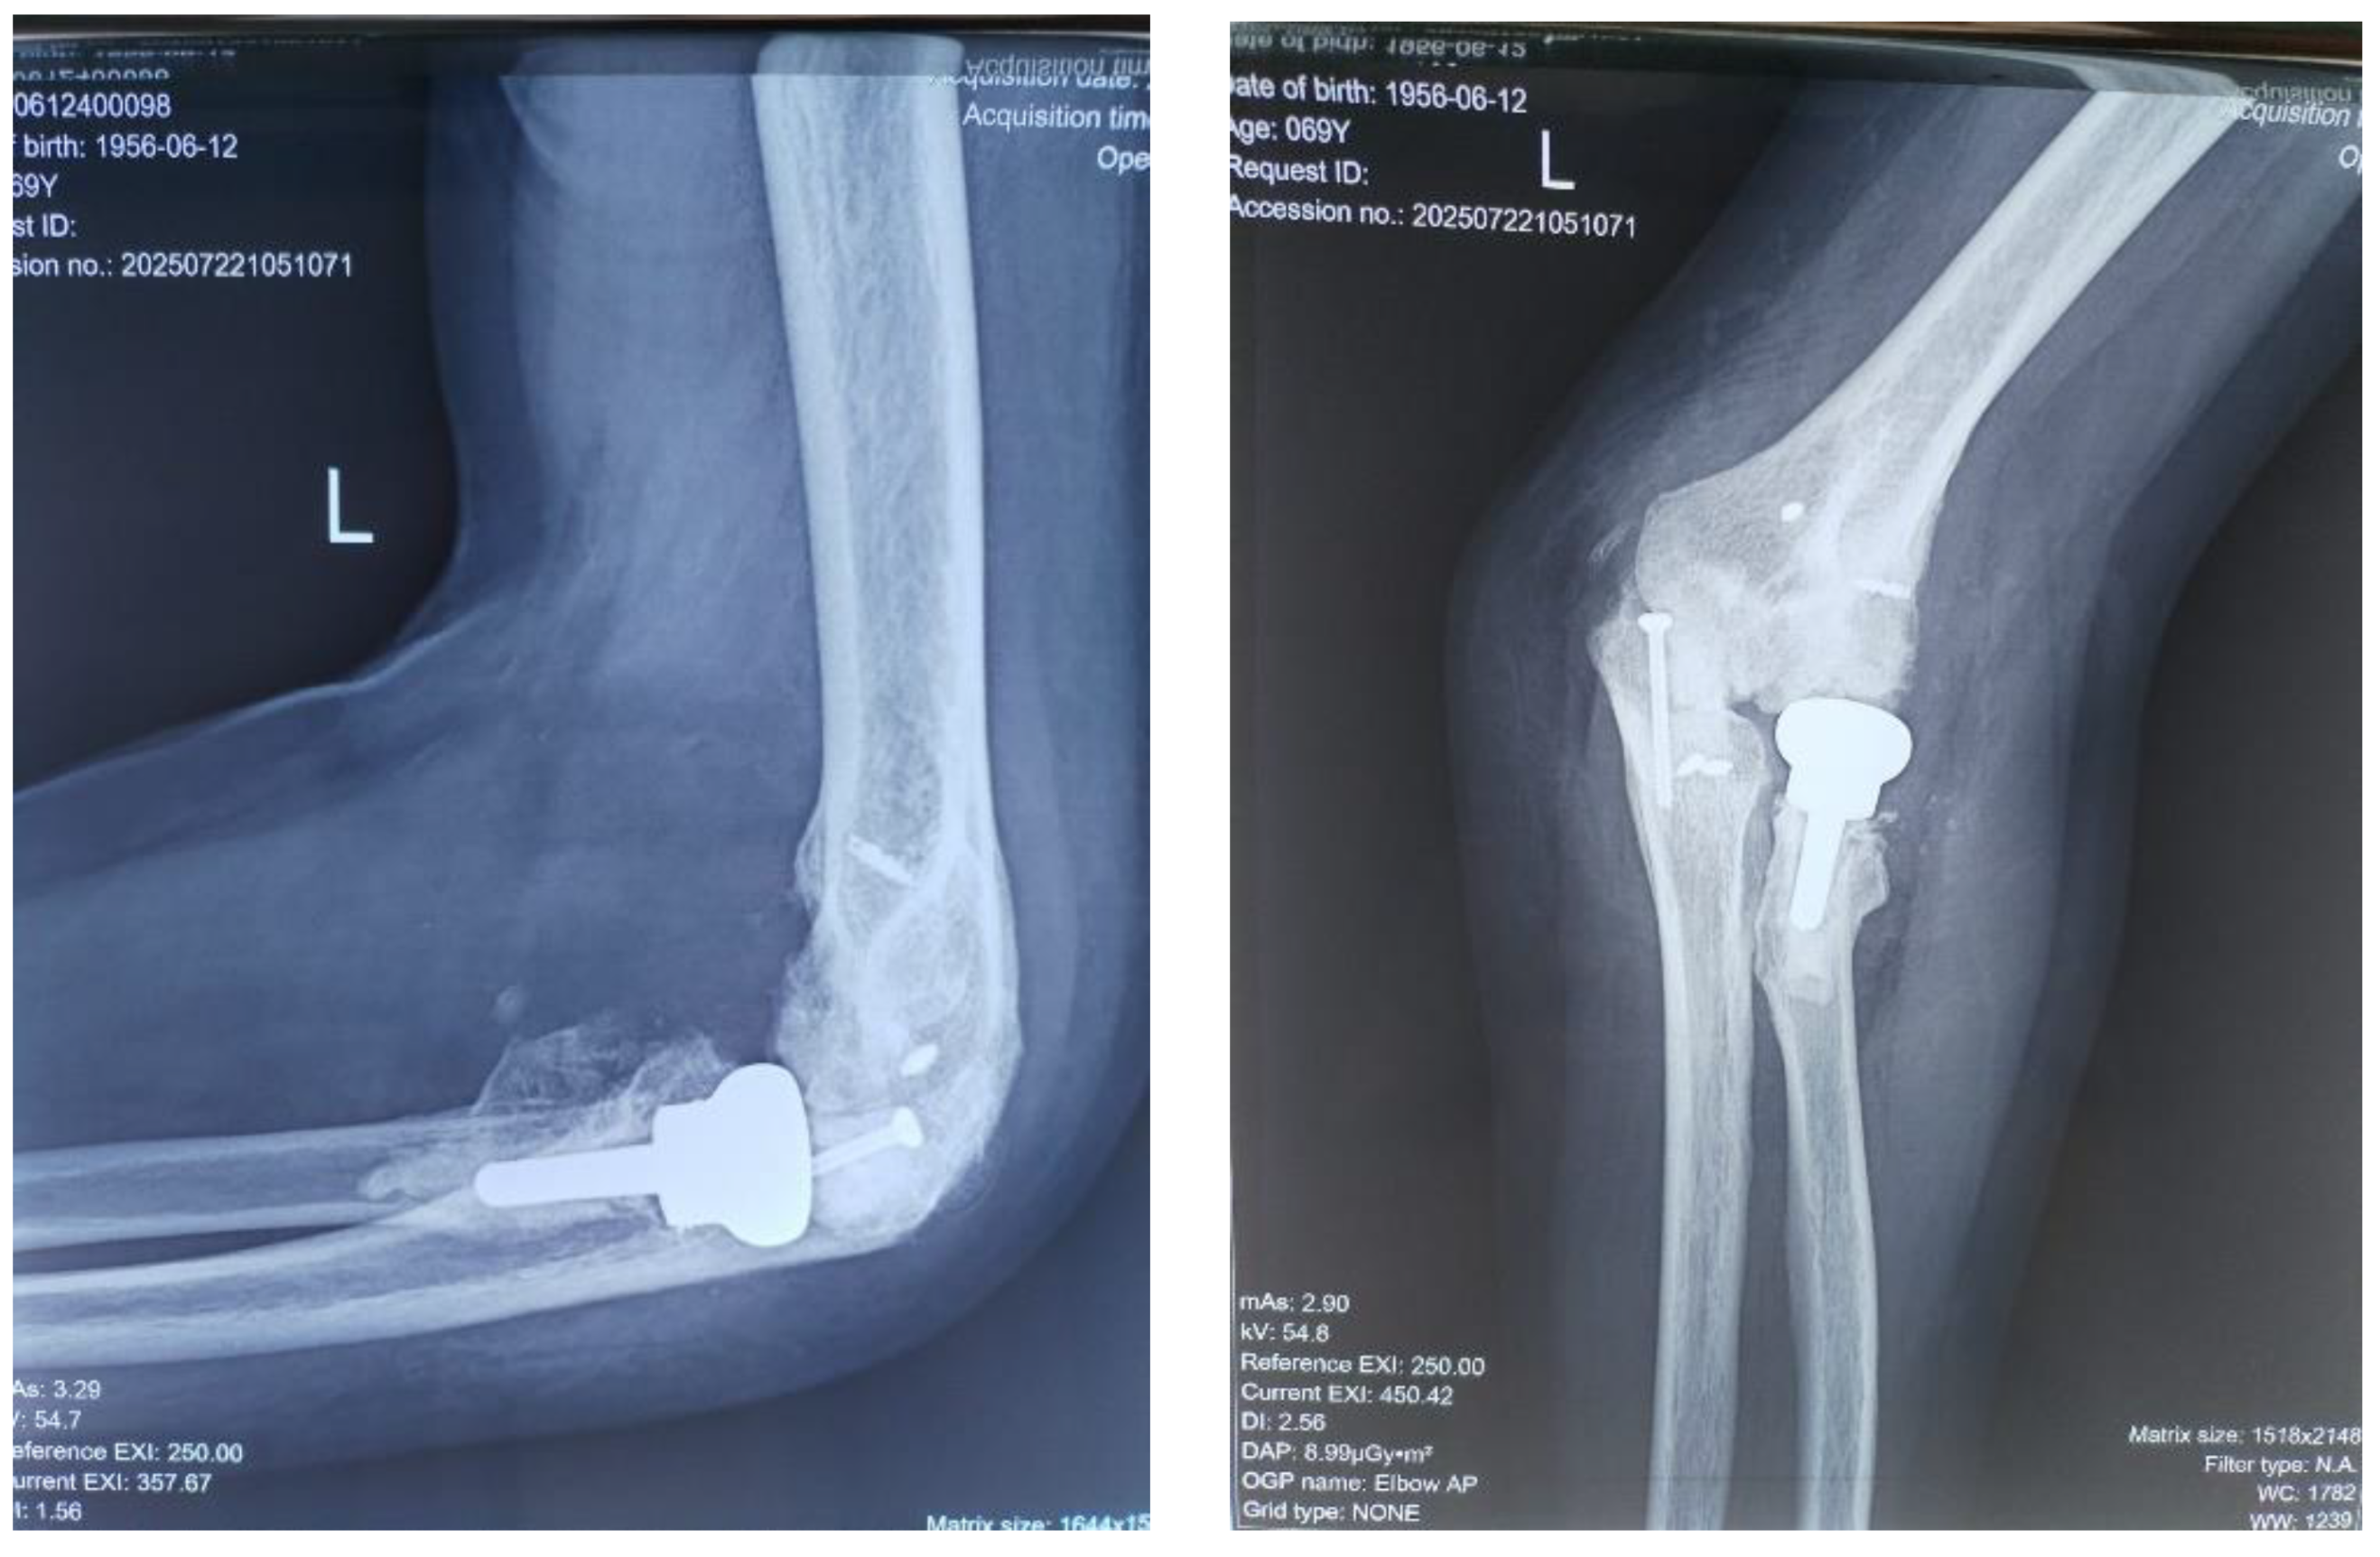

At the time of injury, the diagnosis of posterior elbow dislocation with associated fractures was not fully recognized. The patient underwent closed reduction and cast immobilization, but we did not have access to the initial radiographs taken immediately after the trauma and following the first reduction. The radiographs presented at the time of admission to our clinic were inconclusive due to heterotopic ossification, so a 3D computed tomography (CT) scan was requested to provide a more accurate depiction of the bony anatomy and the relative position of the joint structures (Figure 2). The CT scan revealed a chronic posterior dislocation of the elbow, accompanied by a large heterotopic bony mass within the joint space. The coronoid process of the ulna was no longer identifiable, suggesting it had been either resorbed or fragmented at the time of injury. Additionally, the radial head was found to be severely deformed (Masson 3), impeding normal articulation with the capitulum and rendering the proximal radioulnar joint functionally blocked.

Figure 2. 3D CT aspect with visualisation of dislocation and presence of a massive heterotopic bone inside the joint.